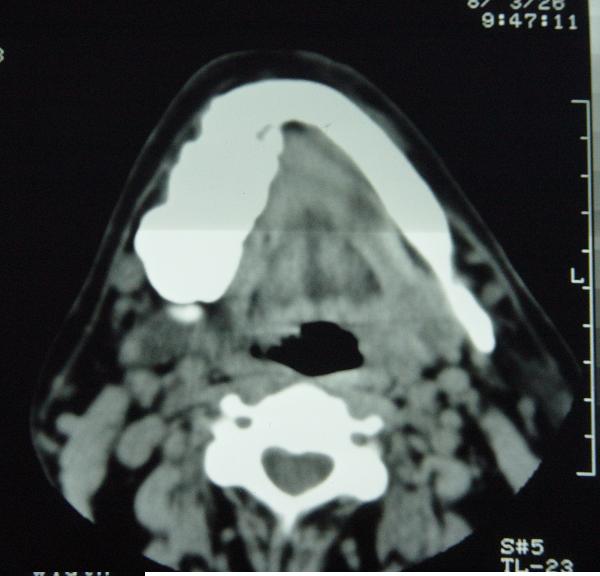

标题: CT12465:下颌骨肿瘤,请会诊 [打印本页]

标题: CT12465:下颌骨肿瘤,请会诊

发现下颌骨肿瘤近30年.逐渐增大.

考虑右侧下颌骨水平部及升部骨纤维异常增殖症可能性大。